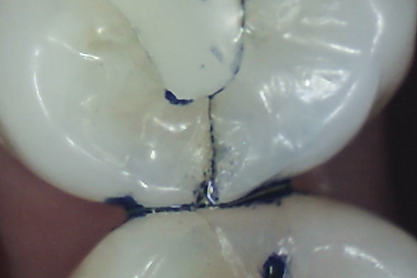

The detrimental effects of vertical cracks on the dentition and surrounding tissues stem mostly from bacterial invasion into the microscopic space of the crack, as well as physical irritation and liquid microleakage, even though the separation of the segments may not be clinically visible.3,5-7As bacteria penetrate cracks, they invade underlying structures, such as the coronal dentin, pulp, root structure, and periodontal tissues, leading to varying degrees of pathologies. Enamel cracks have been found to provide caries-producing bacteria access to the dentin-enamel junction, leading to caries inside the tooth without any externally visible evidence (Figure 1).5 Dentin cracks are pathways of bacteria to the dentinal tubules and pulp, leading to various pulpal pathologies, including reversible and irreversible pulpitis and pulp necrosis.6,8

Fig 1. Decalcification in enamel along a crack line (arrow) and caries at the dentin-enamel junction of a mandibular left first molar (disto-occlusal view).

Figure 1